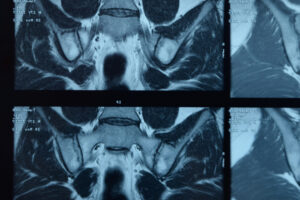

Podstawowym badaniem obrazowym jest rezonans magnetyczny prostaty (mpMRI), który umożliwia precyzyjną ocenę ognisk nowotworowych, ich agresywności oraz relacji do torebki prostaty, pęcherzyków nasiennych i cewki moczowej. Wyniki mpMRI pomagają w podjęciu decyzji o zakresie operacji oraz w ocenie ryzyka zajęcia węzłów chłonnych.

Rezonans magnetyczny miednicy jest obecnie uznawany za złoty standard w ocenie miejscowego zaawansowania raka szyjki macicy. Badanie pozwala precyzyjnie określić wielkość guza, jego lokalizację oraz stopień naciekania sąsiednich struktur, takich jak trzon macicy, pochwa, przymacicza czy ściany miednicy. To ma kluczowe znaczenie przy kwalifikacji pacjentki do leczenia operacyjnego, radioterapii lub leczenia skojarzonego.

Obraz MRI umożliwia dokładną ocenę wielkości guza, jego naciekania na sąsiednie struktury (takie jak przymacicza, pochwa czy ściana miednicy) oraz ewentualnego zajęcia węzłów chłonnych. Powyższe dane pozwalają zespołowi terapeutycznemu podjąć świadomą decyzję, czy pacjentka kwalifikuje się do leczenia operacyjnego, czy też bardziej wskazana będzie radioterapia lub radiochemioterapia. W przypadku planowania zabiegu chirurgicznego MRI pomaga określić zakres operacji i zmniejszyć ryzyko niedoszacowania choroby, natomiast w radioterapii umożliwia precyzyjne zaplanowanie pól napromieniania, co zwiększa skuteczność leczenia i ogranicza uszkodzenie zdrowych tkanek.

Rezonans magnetyczny miednicy jest jednym z najdokładniejszych badań obrazowych stosowanych w diagnostyce schorzeń narządów położonych w obrębie miednicy mniejszej. Dzięki wysokiej rozdzielczości i możliwości oceny tkanek miękkich bez użycia promieniowania jonizującego, rezonans odgrywa kluczową rolę w rozpoznawaniu chorób nowotworowych, stanów zapalnych oraz zmian anatomicznych. Rezonans miednicy znajduje zastosowanie zarówno u kobiet, jak i u mężczyzn, często stanowiąc uzupełnienie lub kolejny etap diagnostyki po badaniu USG lub tomografii komputerowej.

Rezonans magnetyczny (MRI) miednicy to nieinwazyjne, bezpieczne badanie obrazowe, które pozwala na bardzo dokładną ocenę struktur anatomicznych znajdujących się w obrębie miednicy mniejszej. W przeciwieństwie do badań wykorzystujących promieniowanie rentgenowskie, rezonans magnetyczny opiera się na działaniu silnego pola magnetycznego oraz fal radiowych, dzięki czemu nie obciąża organizmu promieniowaniem jonizującym.

MRI umożliwia ocenę tkanek miękkich z dużą precyzją, co ma szczególne znaczenie w diagnostyce chorób narządów rozrodczych, układu moczowego, jelit oraz struktur naczyniowych i mięśniowych miednicy. Rezonans magnetyczny miednicy może być wykonywany zarówno bez użycia środka kontrastowego, jak i z jego podaniem dożylnym. Kontrast poprawia widoczność zmian patologicznych, takich jak guzy, stany zapalne czy nieprawidłowości naczyniowe, i jest stosowany wtedy, gdy lekarz potrzebuje dokładniejszej oceny charakteru wykrytych zmian.